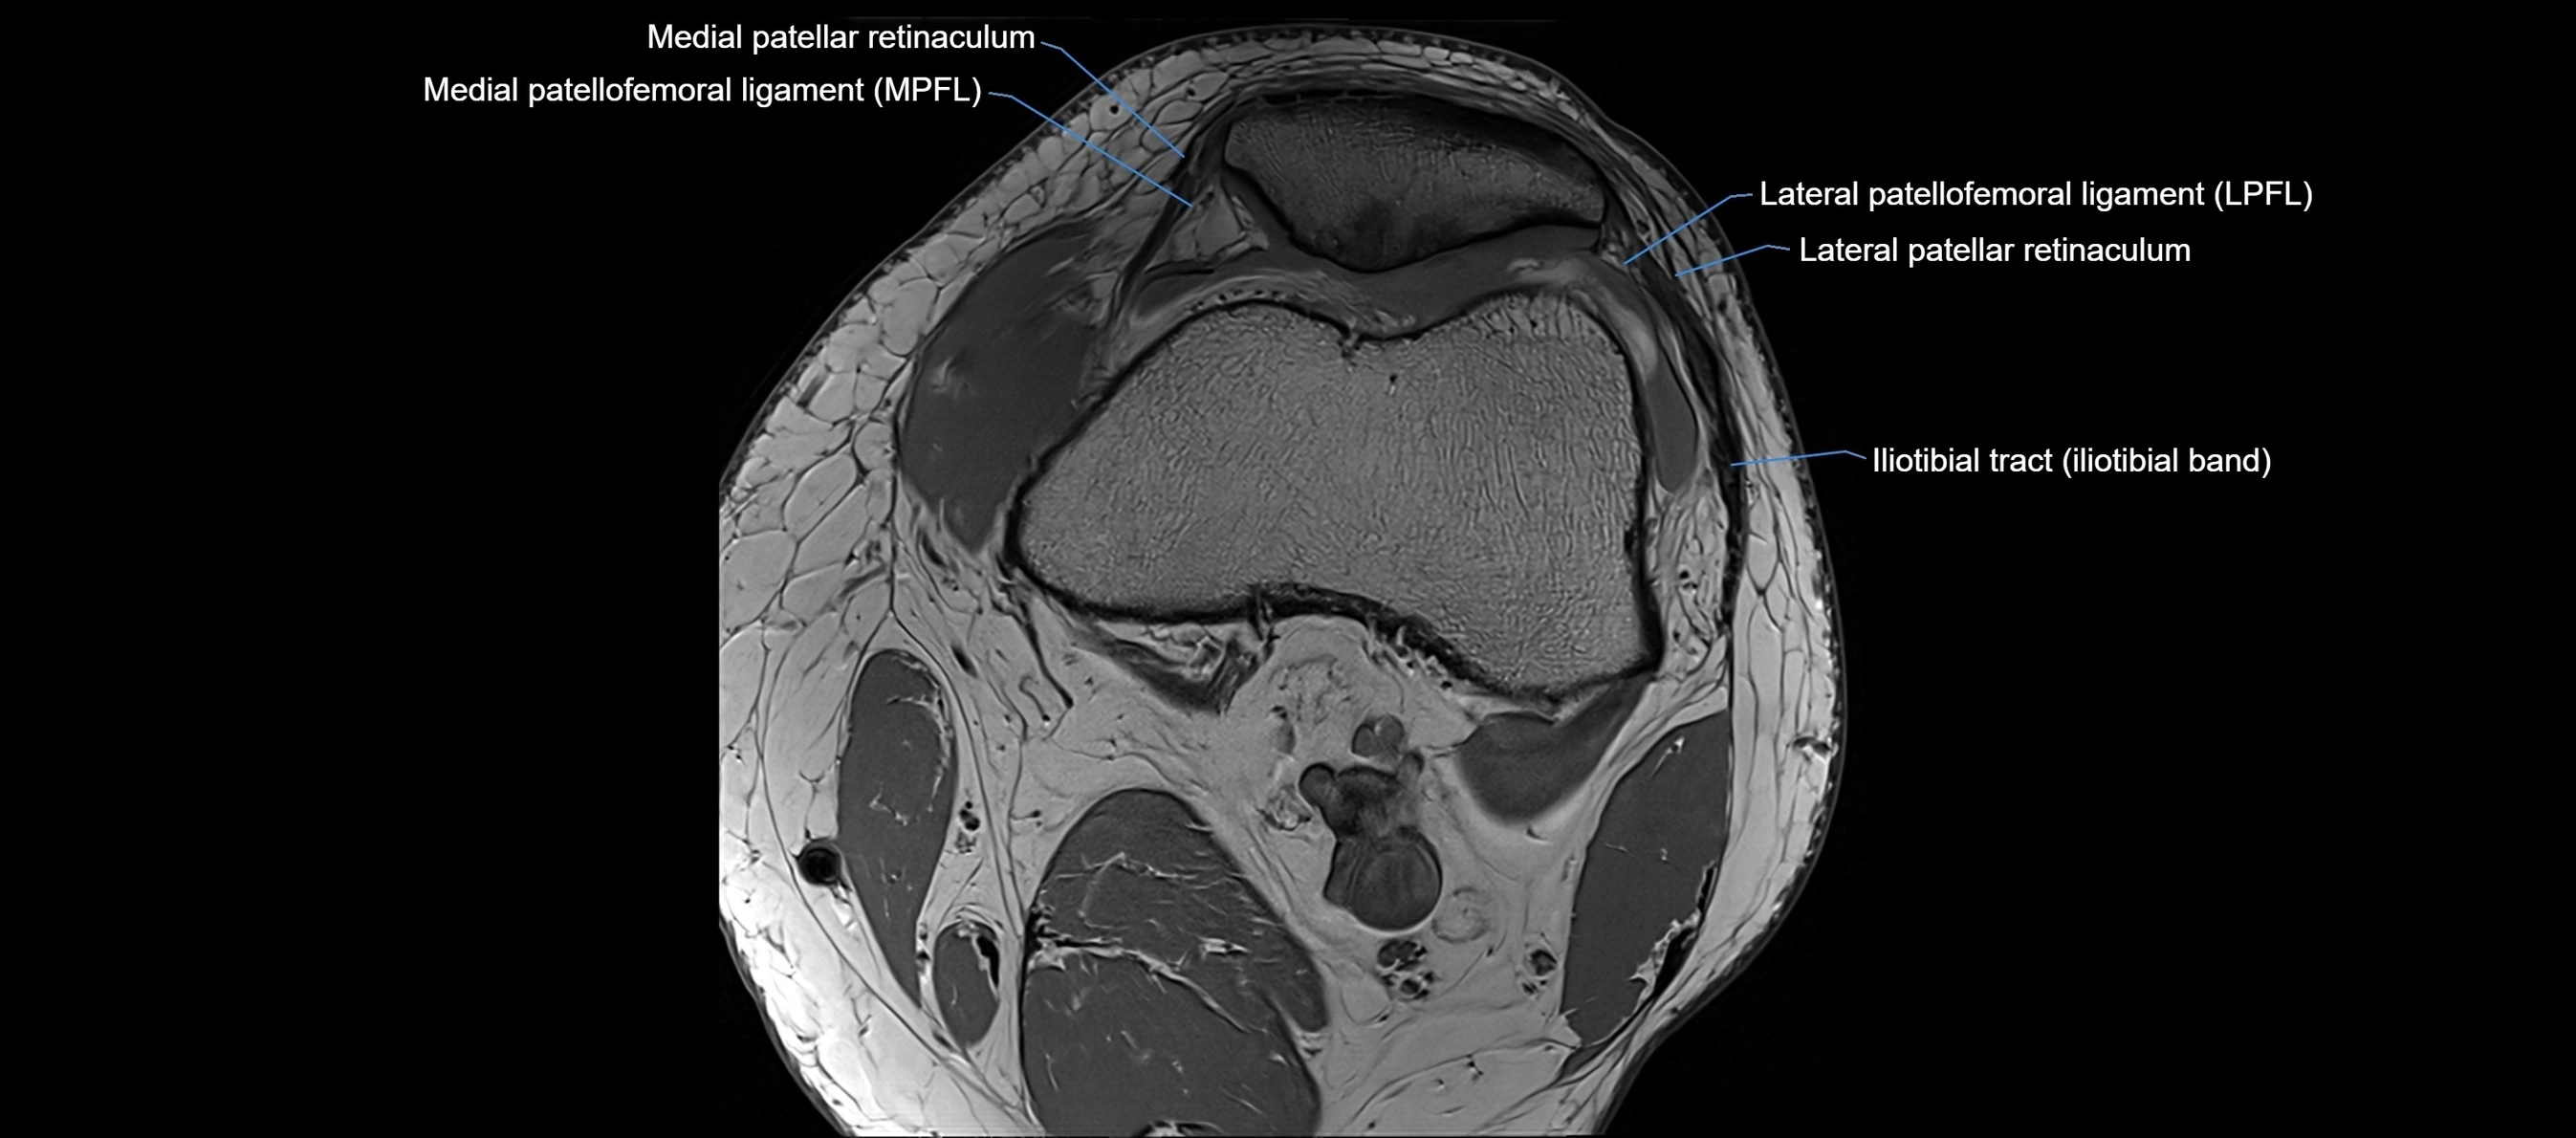

MRI images

image